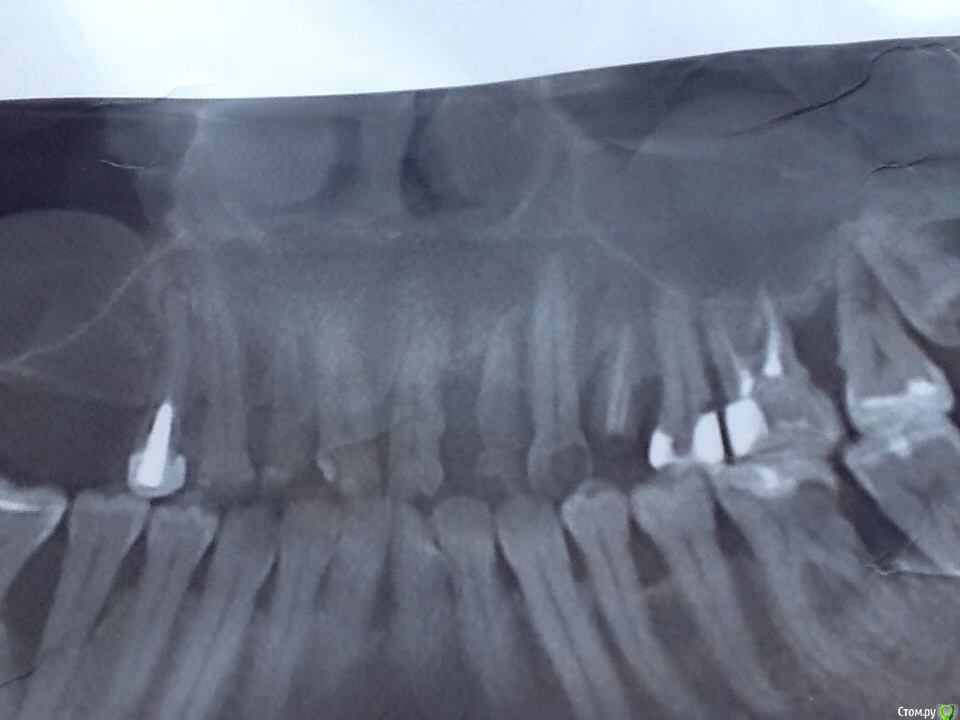

NoSpane Опубликовано 27 марта, 2017 Поделиться Опубликовано 27 марта, 2017 Добрый день, уважаемые доктора! Нужен ваш профессиональный совет касательно удаления всех ( ?! ) зубов мудрости и проблем с оставшимися жевательными зубами. Прокомментируйте, пожалуйста, весь снимок - что и как нужно делать! Хотелось бы сохранить хотя бы нижние " семерки" , но местные стоматологи соглашаются только на вариант удаление 7,8 в паре либо просто не берутся . По поводу верхней челюсти тоже разноречивые мнения - парно удалять, либо вначале 7, потом 8. В случае перфорации пазухи тоже разделились во мнениях- КАК ушивать и ушивать ли вообще Удалять по частям не хотят, предлагают целиком дергать Хотя сразу же мельком обмолвились, что не гарантируют сохранность челюсти при таком удалении Ходила-ходила по врачам, только время потеряла - в итоге полная неразбериха в голове Одинаковых мнений у врачей нет и какому специалисту довериться я не знаю Помогите, пожалуйста, определиться!!! Буду благодарна за любое мнение! Ссылка на комментарий

St. Опубликовано 28 марта, 2017 Поделиться Опубликовано 28 марта, 2017 Да оставьте в покое 7, не надо их ни депульпировать профилактически, ни удалять. Если не берутся у Вас, едьте в больший город, ищите доктора который возьмется.8 я бы рекомендовала удалить все 4. И да, после удалений лунку обычно ушивают.Еще по этому снимку есть проблемы с десной и другими зубами. Ссылка на комментарий

St. Опубликовано 29 марта, 2017 Поделиться Опубликовано 29 марта, 2017 У Вас на всех зубах уходит кость, и под десной есть камень. Скорее всего десна периодически кровоточат при чистке. Нужно сделать гигиену и снять воспаление с десны. Ссылка на комментарий

St. Опубликовано 29 марта, 2017 Поделиться Опубликовано 29 марта, 2017 Если десна сильно кровит и камней много, их сложно хорошо и с первого раза все убрать. Иногда необходимо несколько визитов чтобы хорошо все очистить. По снимку есть отложения на дальних зубах вверху слева. Укрепить как- нибудь подвижный зуб возможно? Шина ? Это очень временное мероприятие, к сожалению. Ссылка на комментарий